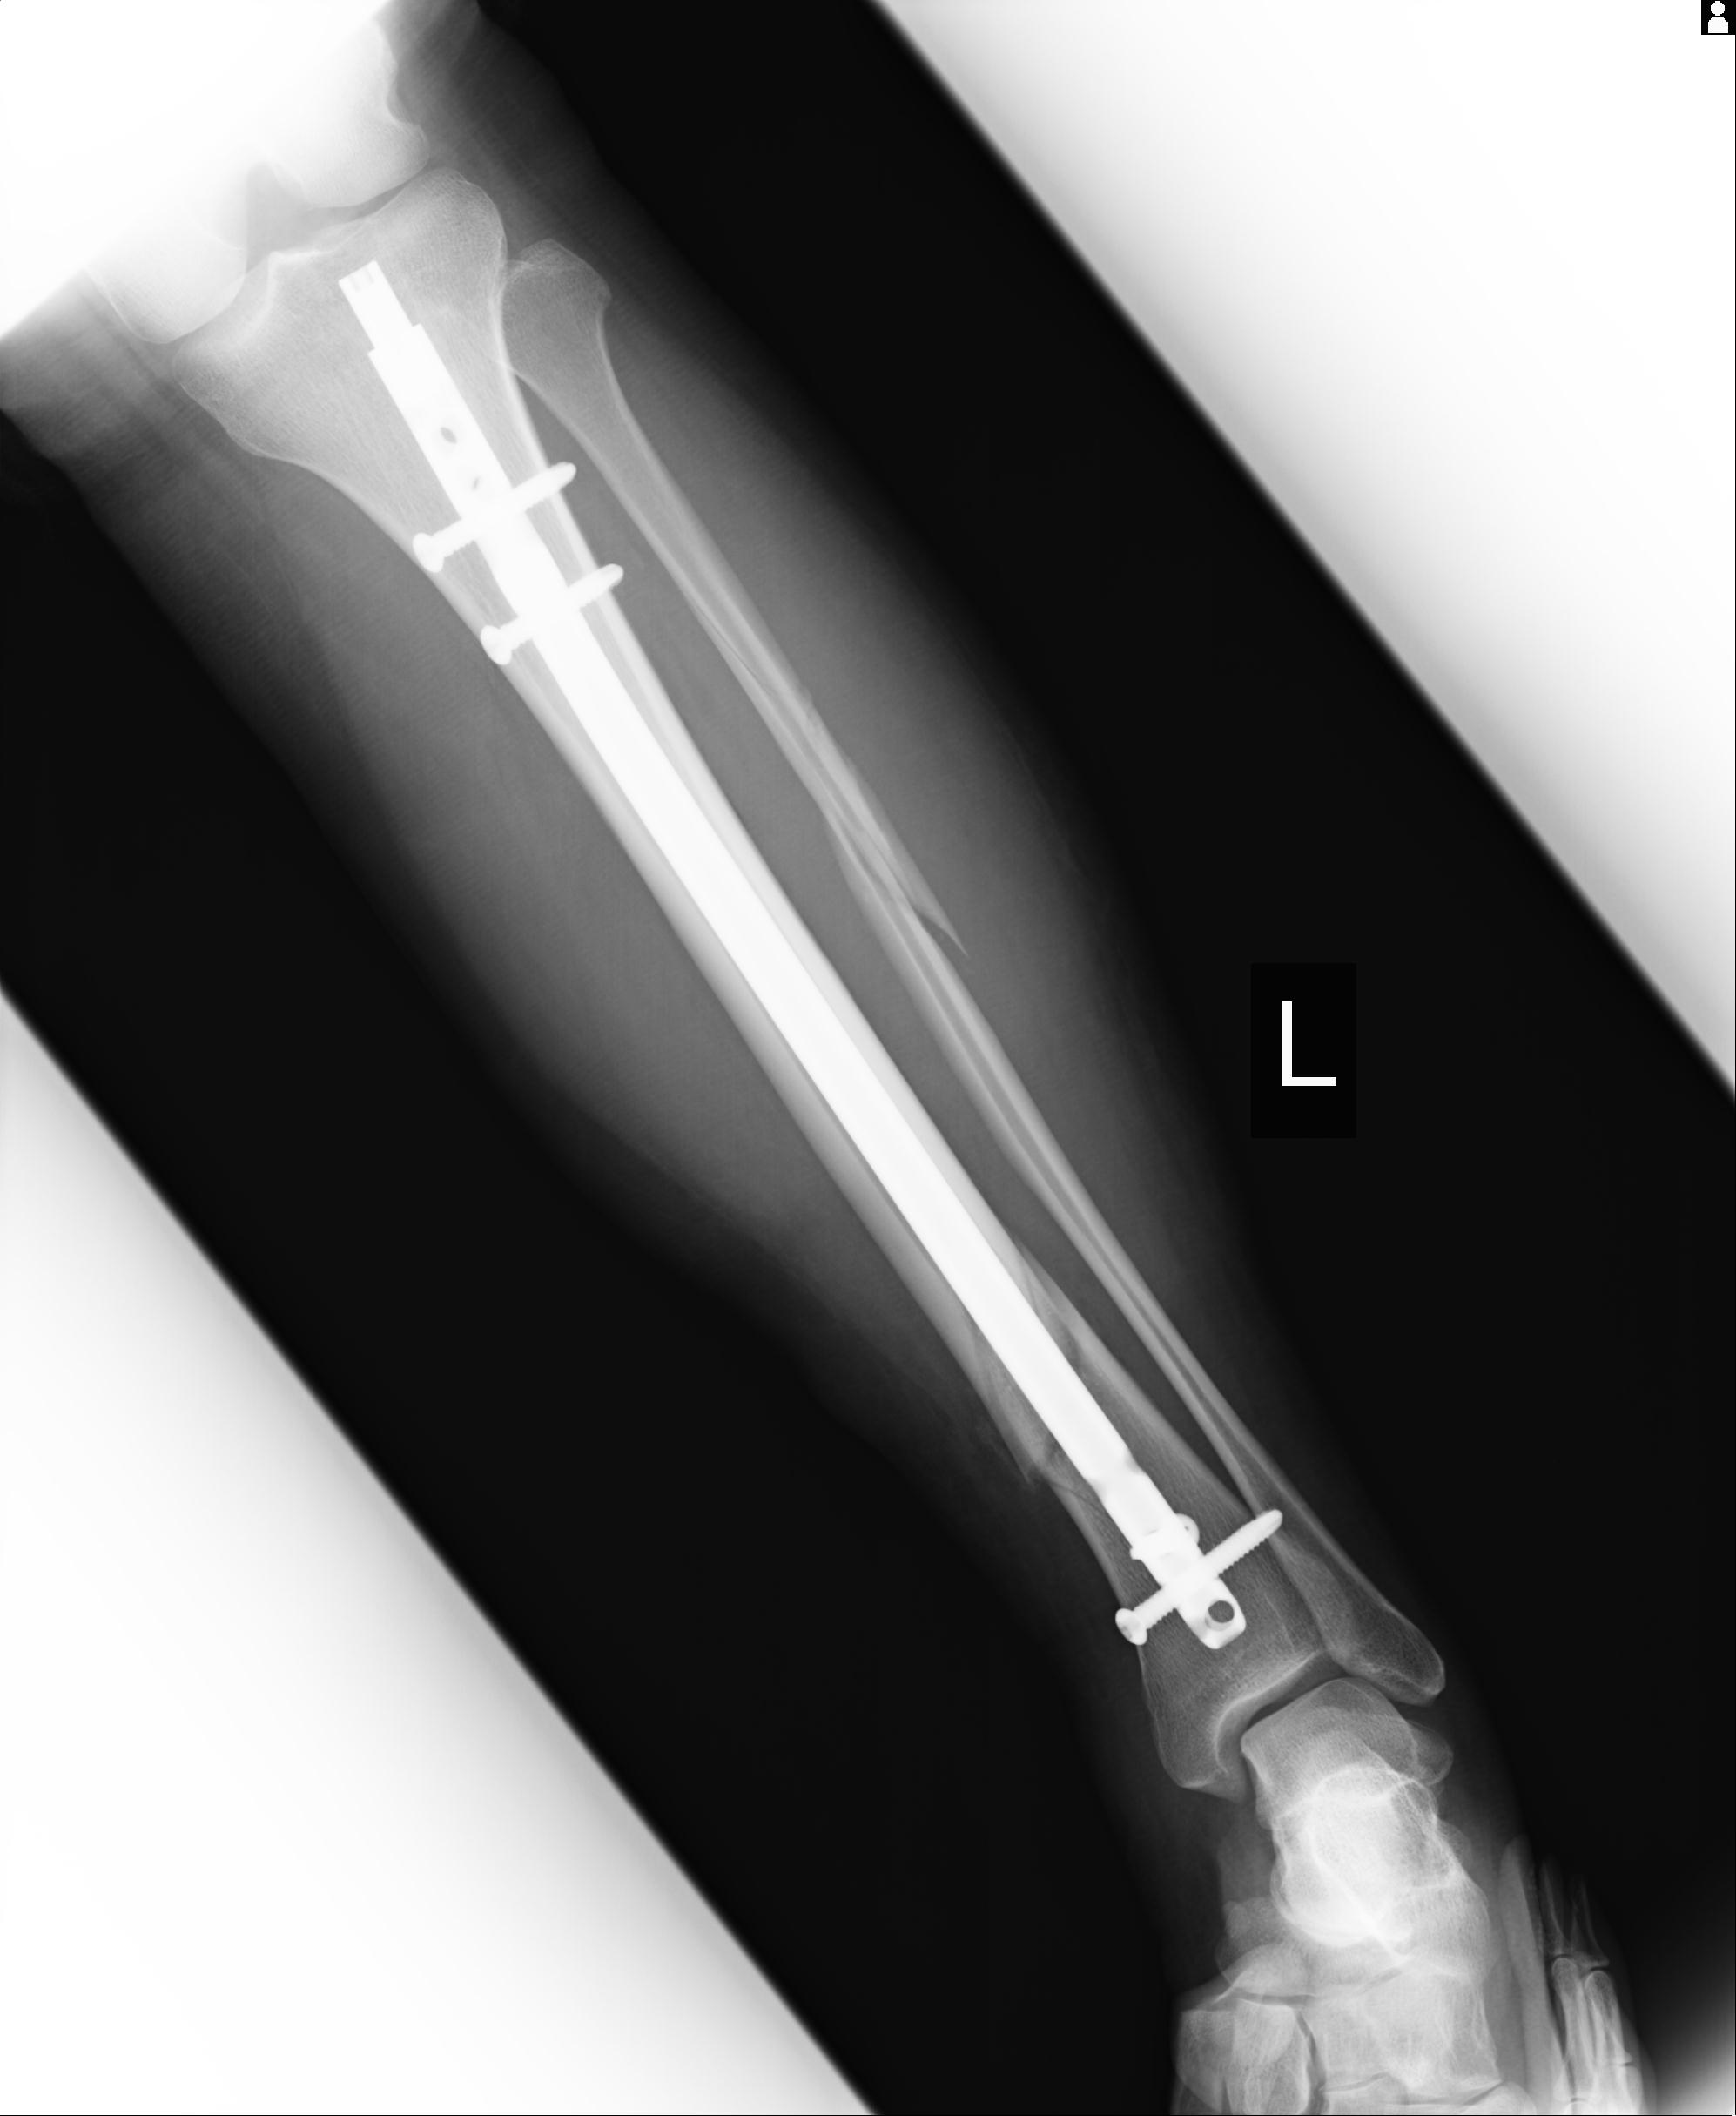

102803 1/12(キウスなし) 1/27 左下腿 4R 30歳女性 左脛骨軸内釘